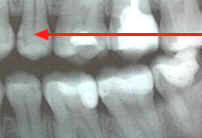

El ICCMS clasifica radiográficamente las superficies posteriores de los dientes (36,37)  Se ha reportado que tanto la reproducibilidad como la precisión de este sistema de clasificación son de significativas (33) a excelentes (37)

La evidencia indica que la profundidad de penetración radiográfica en la que se puede predecir de forma confiable que la superficie del diente está cavitada y que la dentina está muy infectada, es cuando la radiolucidez está más alla del tercio externo de dentina (7,34,35,38,40). Esto corresponde a los códigos 4, 5 y 6 en el sistema de clasificación radiográfica de ICCMS. Ver tabla 6. En casos en que las tasas de progresión son rápidas, se puede esperar que en lesiones con clasificación 3 en el sistema descrito anteriormente, haya formación de cavidad.

Es importante saber que existen diferentes convenciones en diversos países para la clasificación de la severidad de las lesiones en los casos en los que se requiere manejo operatorio. Para poder reducir las variaciones a nivel internacional en este aspecto, se requiere mayor evidencia.

Finalmente, tanto la información radiográfica (cuando está disponible para dientes posteriores) y la valoración clínica terminan clasificando la lesión en las categorías de inicial, moderada o severa. Es importante reconocer la variación entre países en cuanto a la definición de la severidad de la lesión y su equivalencia radiográfica. Esta variación se reducirá en la medida que haya más evidencia.